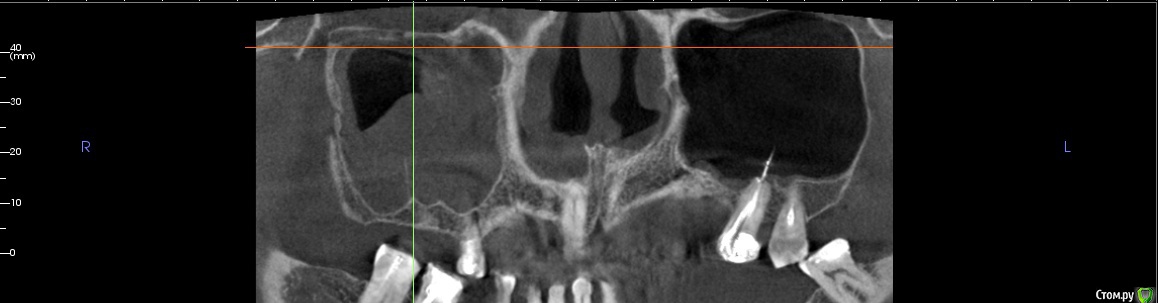

kamranchick Опубликовано 25 декабря, 2017 Автор Поделиться Опубликовано 25 декабря, 2017 (изменено) Чтобы не создавать новую тему...Пациента отправил на санацию ВЧП к лору, но вот такое дал заключение и сказал можно резать, ваше мнение? Изменено 25 декабря, 2017 пользователем kamranchick Ссылка на комментарий

red_butler Опубликовано 25 декабря, 2017 Поделиться Опубликовано 25 декабря, 2017 Другие ЛОРы по близости есть? Я бы до санации пазухи не лез. Ссылка на комментарий

егорджан Опубликовано 26 декабря, 2017 Поделиться Опубликовано 26 декабря, 2017 слева главное штырь торчит на сантим в пазуху и ничего Ссылка на комментарий

kamranchick Опубликовано 26 декабря, 2017 Автор Поделиться Опубликовано 26 декабря, 2017 слева главное штырь торчит на сантим в пазуху и ничегоштырь торчит 10 лет, полет нормальный, закапсулировался, у нас в стране имплантаты вгоняют так в пазуху и так же все хорошо() Ссылка на комментарий

Bier Опубликовано 26 декабря, 2017 Поделиться Опубликовано 26 декабря, 2017 ретенционку удали сам, через верхний доступ, этажем ниже делай синуслифт, если боишься, то в 2 этапа. Ссылка на комментарий

Irouil Опубликовано 27 декабря, 2017 Поделиться Опубликовано 27 декабря, 2017 Имхо не ретенционная, соустье вероятно перекрыто. Ссылка на комментарий